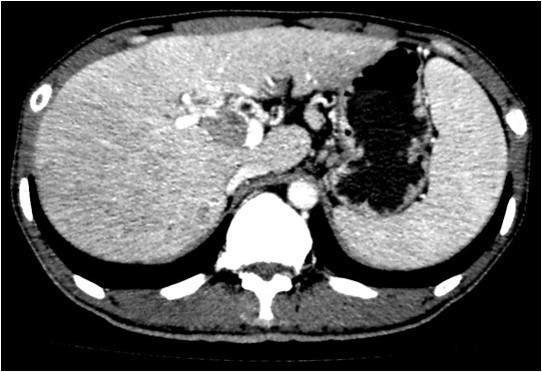

体查:未见阳性体征 实验室检查: WBC 7.24× 109/L, N 48.1%, Hb 159g/L, PLT 117× 109 /L ,PT 12.5s ; HBsAg+, HBcAb+,HBeAg+;HBV-DNA5.33× 106 IU/mL ALT 240 U/L, AST 154 U/L, ALB 36.9g/L, TBIL 13.1umol/L AFP 6270 ug/L ICG 15分钟滞留率 4.5%;Child-Pugh A级 CT提示肝S5、S6肝细胞癌并门静脉右支癌栓形成

诊断: • 肝细胞癌 • 门静脉右支癌栓 治疗:右半肝切除、门静脉取癌栓、胆囊切除术 术后病理: • 肝细胞癌,梁索型,II级,癌旁组织呈门脉性肝硬化改变 • 门静脉内组织呈现肝细胞癌改变伴坏死,符合癌栓改变